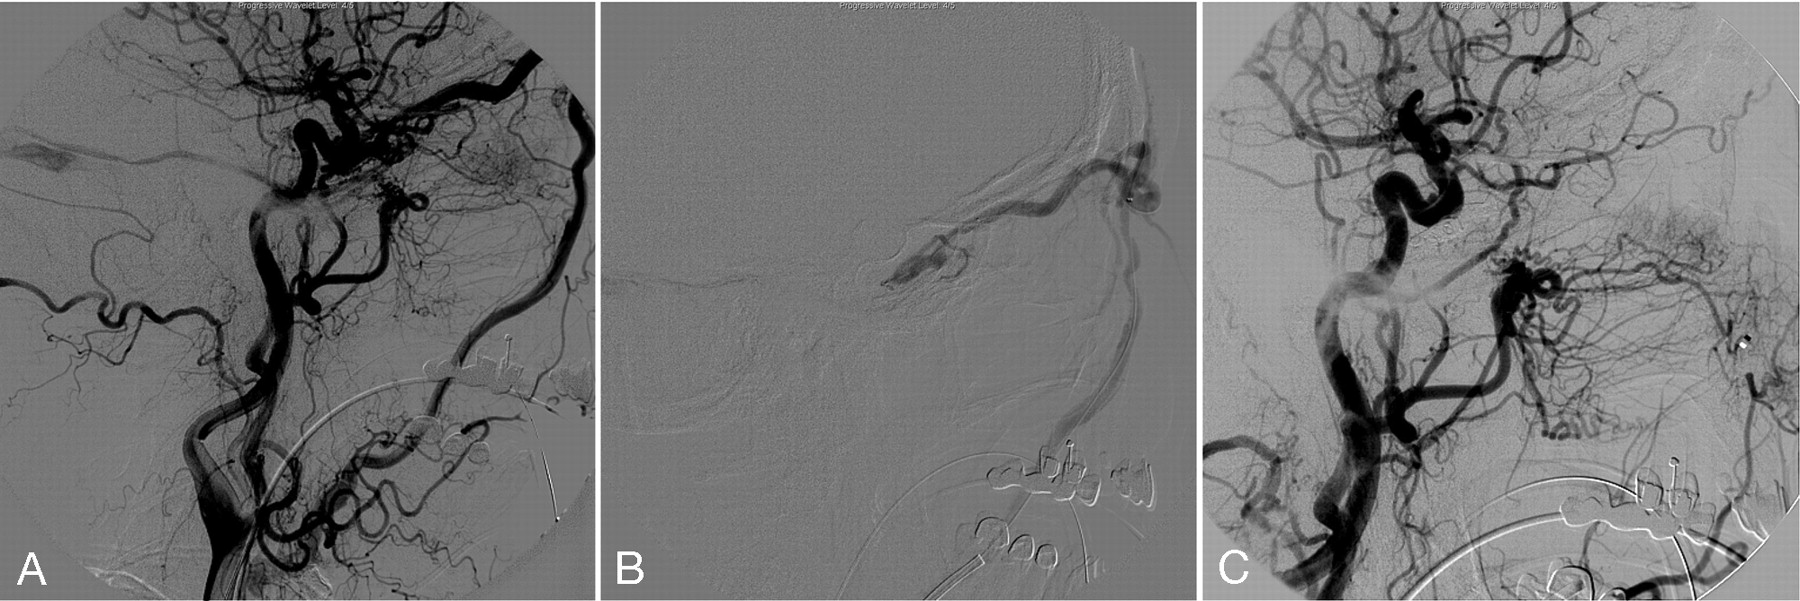

A 64-year-old right-handed woman had acute onset of double vision associated with mild-to-moderate retro-orbital pain. The symptoms progressed with right eye bulging, and redness. The patent denied recent history of head trauma. On examination, there was significant proptosis and chemosis on the right eye, and vertical and lateral movement of the right eye were limited. No bruit was audible. MR imaging and an MRA of the brain disclosed a prominent right SOV, consistent with dural CCF. A cerebral angiogram confirmed the right dural CCF with feeders from meningohypophyseal trunk, leading to early venous drainage into the left SOV (Fig 3A). The IPS and SPS appeared to be occluded secondary to thrombosis. There was no evidence of cortical venous reflux. No contribution of ECA was appreciated. Initial attempts to catheterize the fistula via the transfemoral venous approach through the IPS were unsuccessful. A different approach was subsequently selected to access the facial vein via the external jugular vein. The external jugular vein was selected with the tip of the 6F Envoy angled guiding catheter, then a 5F nontaper angled Glidecath XP (Terumo, Tokyo, Japan) was positioned in the facial vein. A Prowler 14 microcatheter (Cordis) and a FasDasher 14 microguidewire were successfully advanced into the cavernous sinus/SOV junction region. The cavernous dural fistula was occluded with 6 Trufill Orbits coils (Cordis; Fig 3B) followed by slow injection of Onyx 34. The postembolization angiogram showed complete occlusion of the fistula. The microcatheter was then withdrawn from the reflux Onyx cast (Fig 3C). However, a small piece of Onyx cast was fractured and dislodged in the distal segment of left SVO. A thin adhered Onyx crust was seen over the tip of the microcatheter. There was, however, no angiographic or clinical complication identified. Eye symptoms, including pain and chemosis, were resolved within 24 hours after the procedure.

A, Right CCA injection lateral projection demonstrates dural CCF, with feeders from meningohypophyseal trunk with early venous drainage into the right SOV. The IPS is not visualized. No contribution of ECA was appreciated.

B, Transexternal jugular-facial venous access is seen on the lateral projection with a 5F Glidecath XP in the right facial vein and a Prowler 14 microcatheter in the cavernous sinus/SOV junction, and deployed coils.

C, Postprocedure right CCA angiogram lateral projection shows complete occlusion of the fistula with deployed coil mass and Onyx cast. A small piece of dislodged Onyx cast is also shown in the distal segment of right SOV.